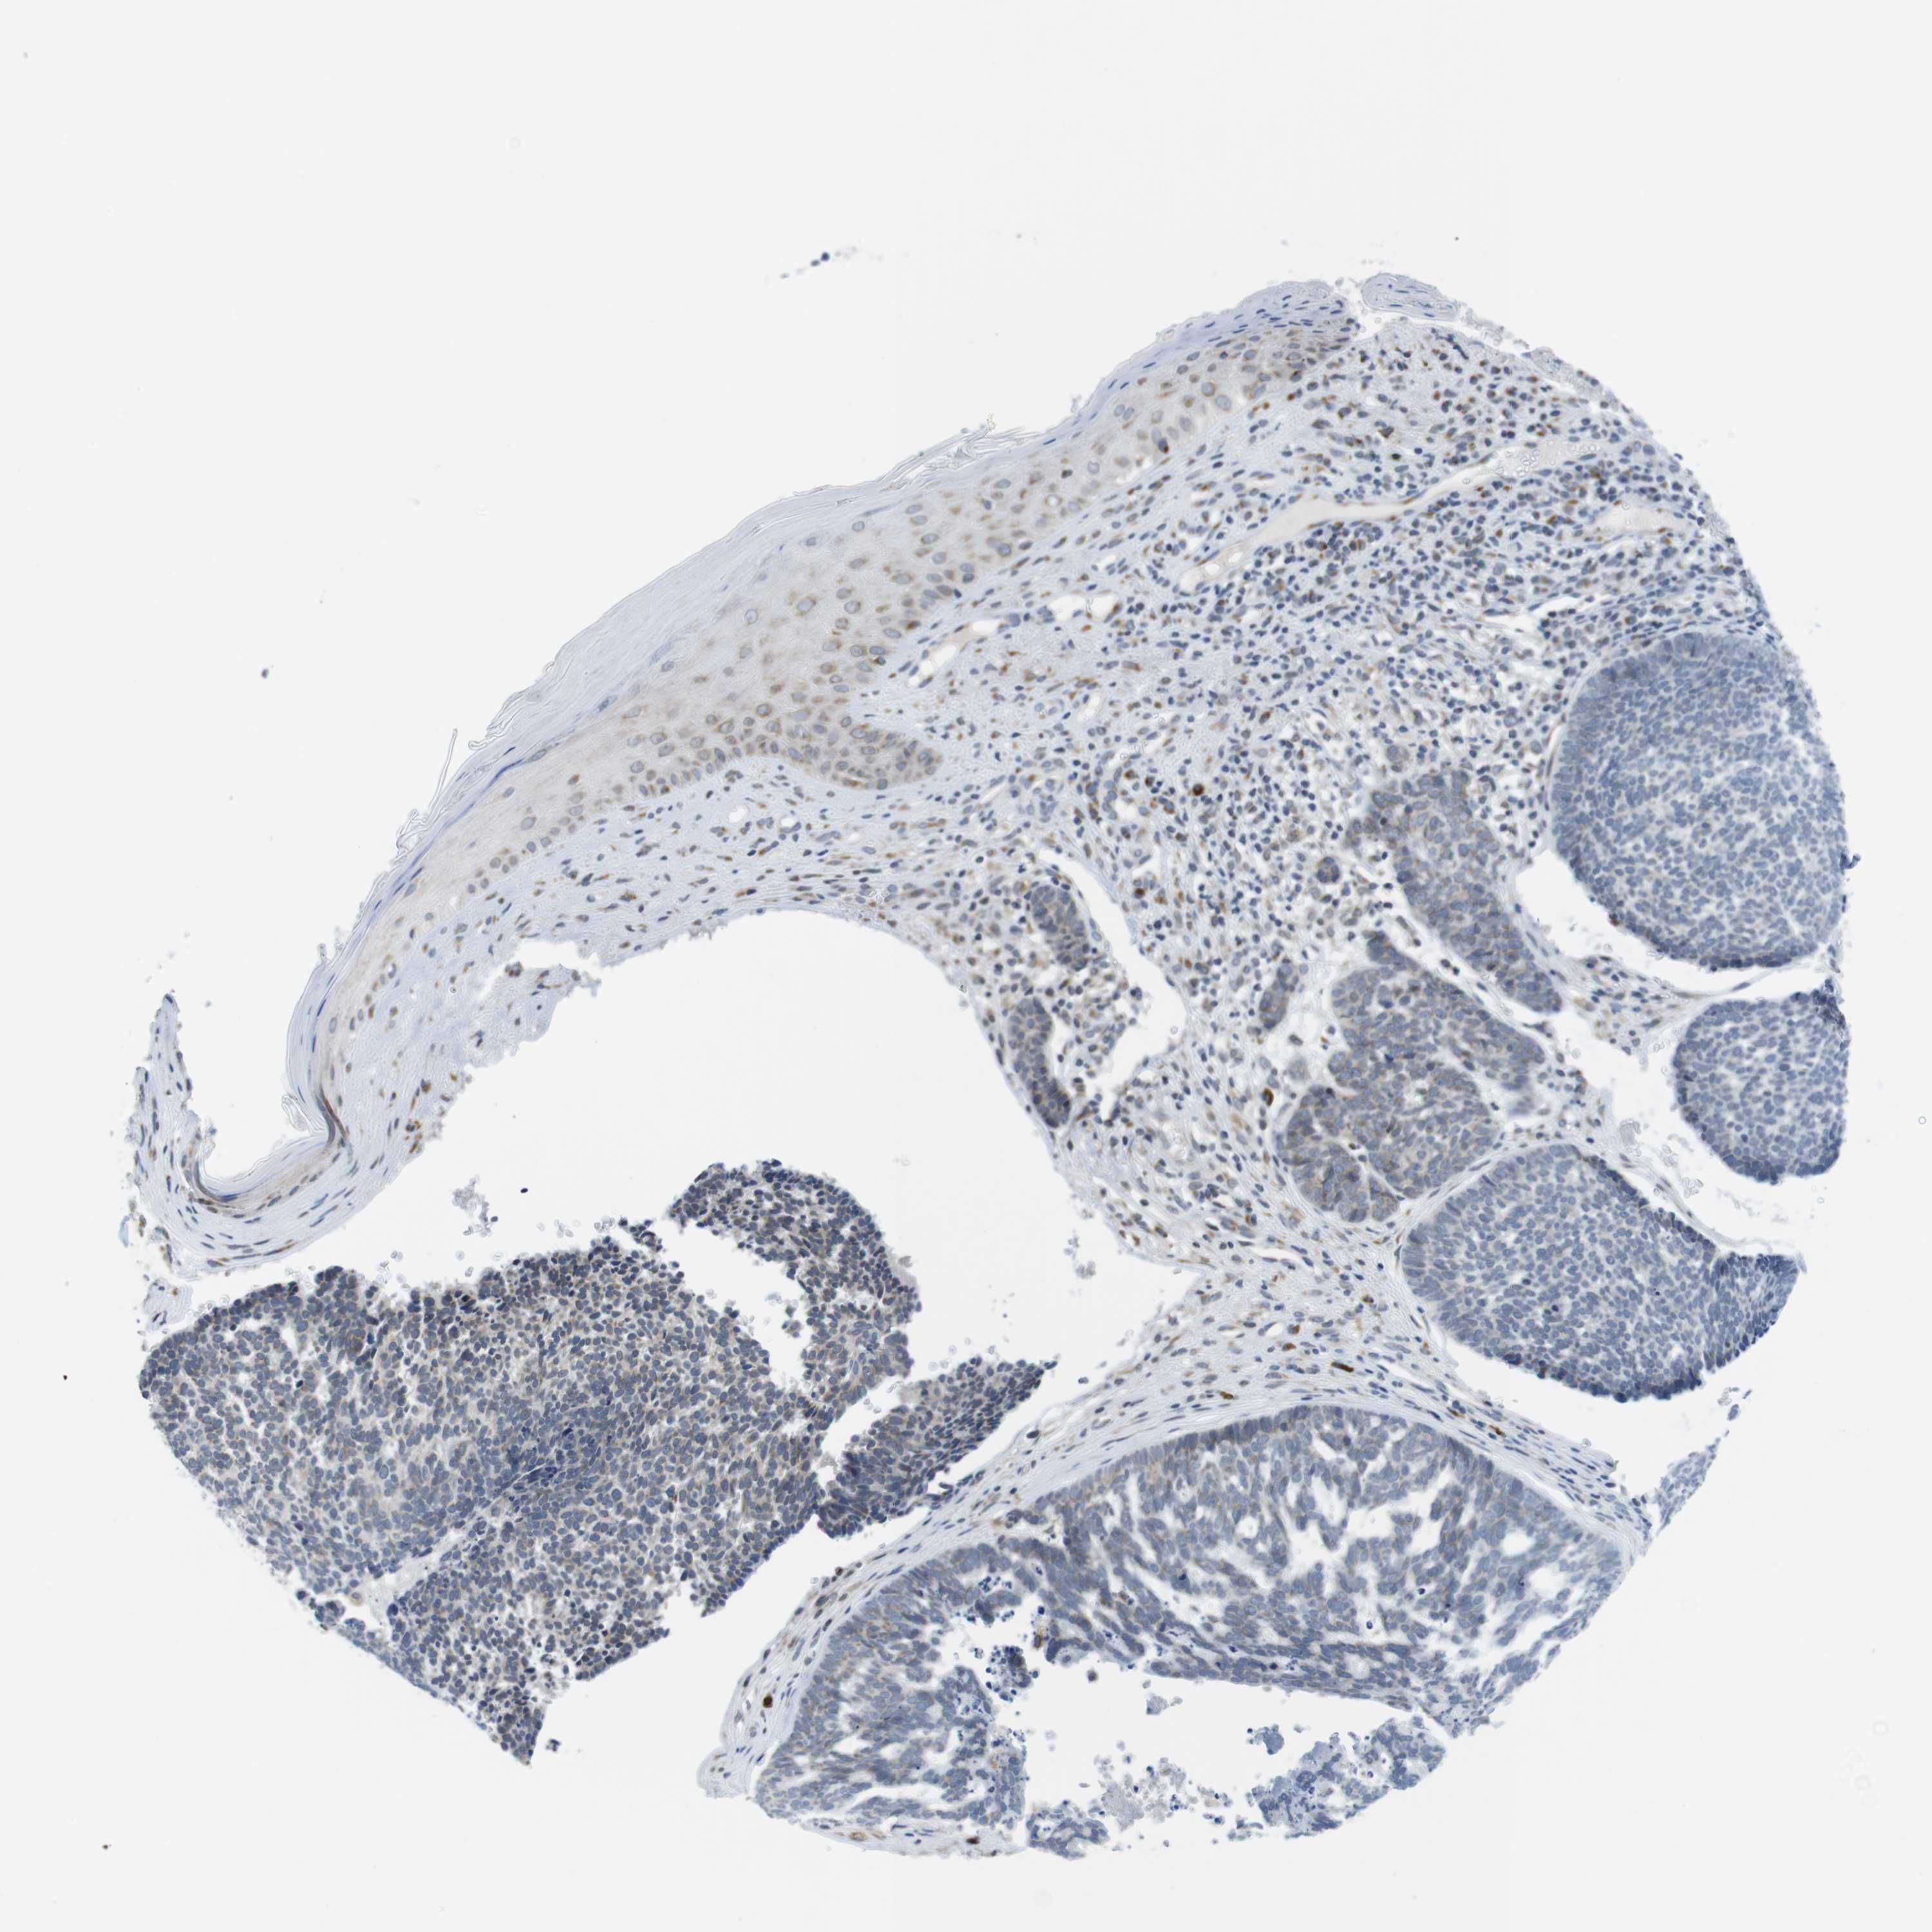

Basal cell and squamous cell cancer

SKIN CANCER - Protein expressioni

A mouse-over function shows sample information and annotation data. Click on an image to view it in a full screen mode. Samples can be filtered based on level of antibody staining by selecting one or several of the following categories: high, medium, low and not detected. The assay and annotation is described here.

Each image is clickable and will lead to virtual microscopy that enables deeper exploration of all samples and also displays staining intensity scores, fraction scores and subcellular localization as well as patient and tissue information for each sample.

Antibody HPA015242

Squamous cell carcinoma, NOS

Squamous cell carcinoma, metastatic, NOS